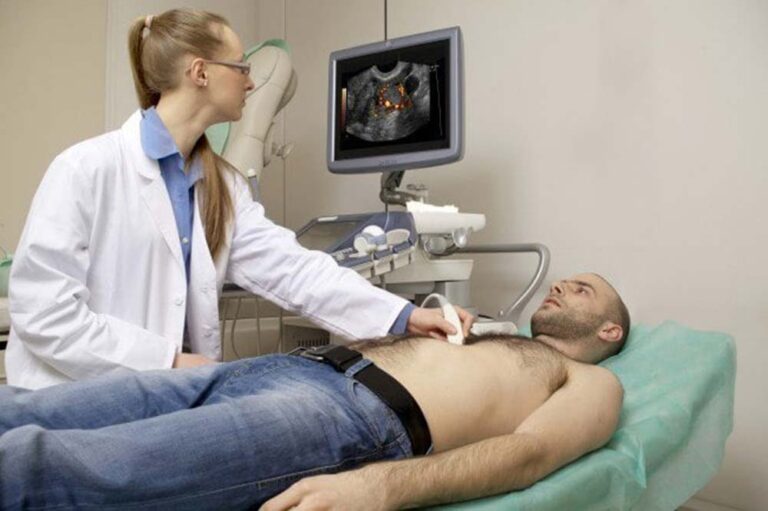

هل عملية قسطرة القلب خطيرة؟ مخاطر قسطرة القلب (القسطرة القلبية) تتضمن العديد من الأمور التي يجب أخذها بالحسبان قبل الخضوع للعملية ولكن عادة ما يكون خطر حدوث مضاعفات كبيرة أثناء إجراء قسطرة القلب التشخيصية أقل من 1٪ ومخاطر الوفاة بنسبة…